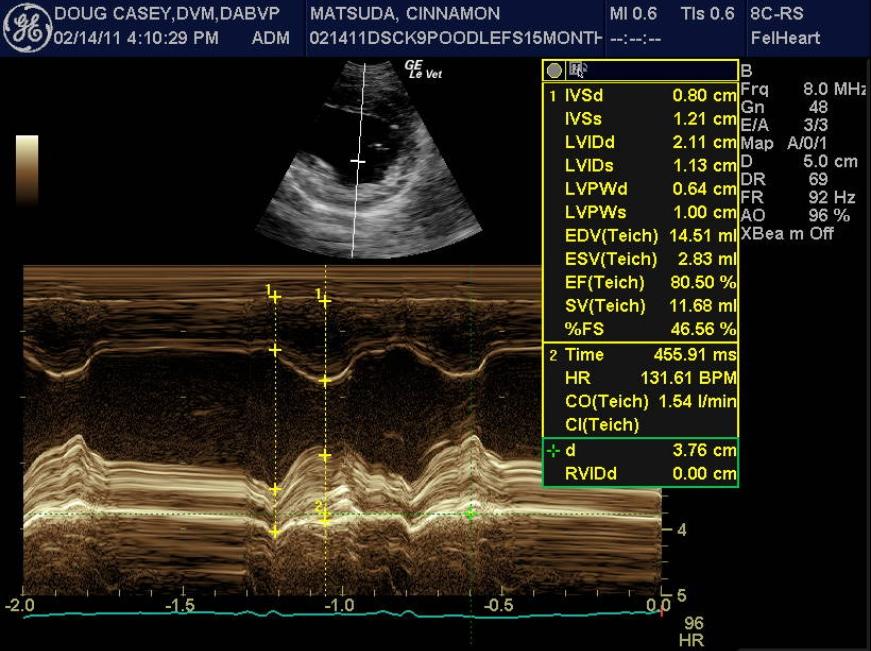

A 1-year-old female spayed toy poodle dog presented for evaluation of bradycardia. Blood pressure was within normal limits. Survey thorax radiographs showed normal size and shape of the cardiac silhouette and left atrium. The vertebral heart sum was 10.2, and a mild interstitial lung pattern was noted.